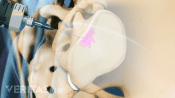

Profile view of the pelvis showing an sacroiliac joint (SI) injection

Accurate Diagnosis of Sacroiliac Joint Dysfunction